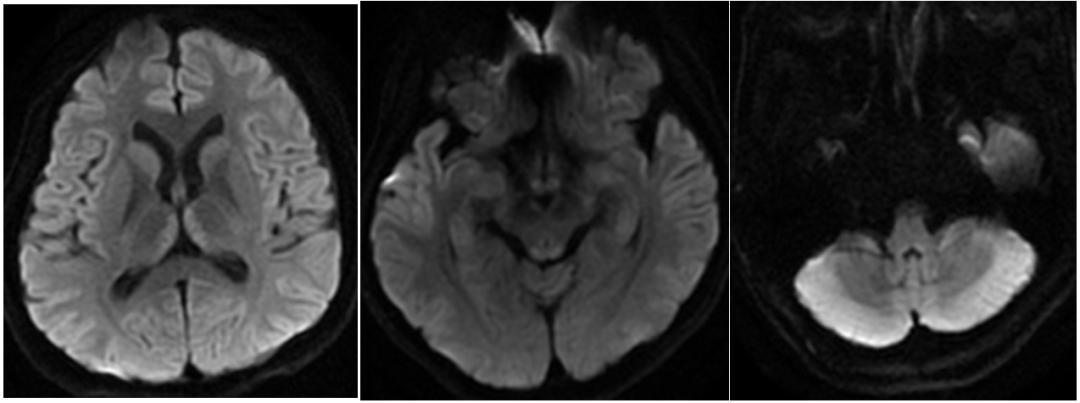

男,73歲,多發(fā)性骨髓瘤化療后惡心、嘔吐1個月。臨床表現(xiàn)為小腦性共濟失調、眼肌麻痹、雙側水平眼震。顱腦DWI示:雙側小腦半球、蚓部彌散受限(A-C)。Flair未見第3腦室周異常信號。復查DWI示:除之前病灶灶(E),還可見雙側乳頭體(F)、中腦頂蓋(G)、丘腦內側(H)彌散受限。